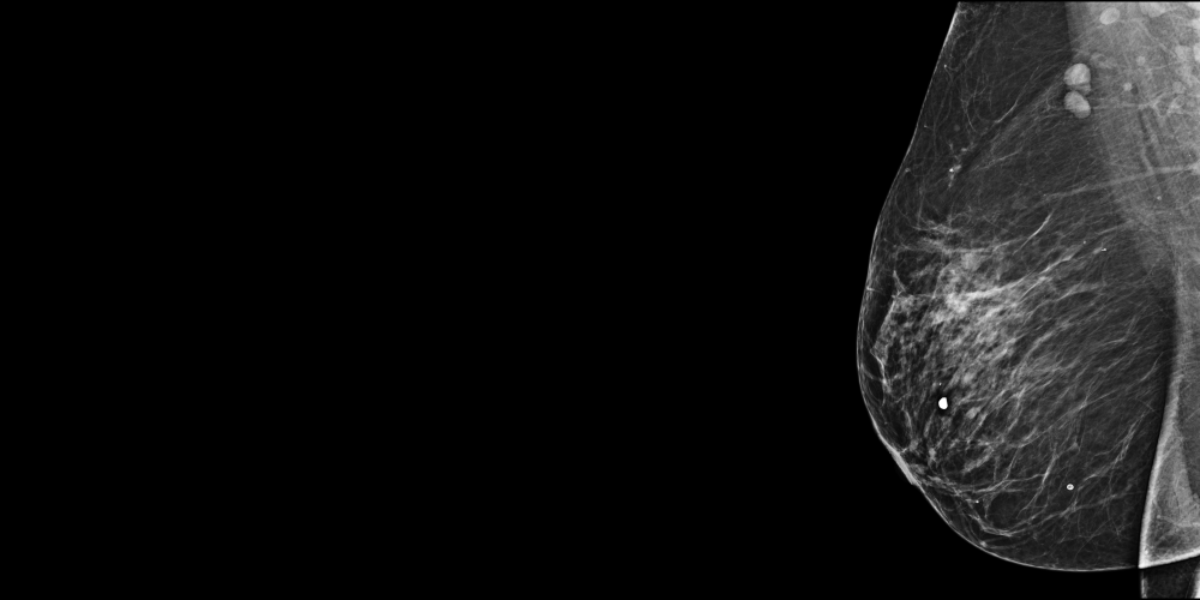

75-year-old woman, one year prior screening mammogram considered normal.

The patient comes back because of a swelling of the right breast (in France screening is usually recommended every 2 years).

MammoScreen® points to a mass in the upper outer quadrant of the right breast.